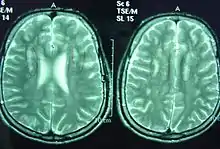

T2-weighted MRI images of a 25-year-old male with Sjögren–Larsson syndrome revealing dysmyelination in the deep periventricular white matter and reduced brain volume in the frontal lobe.